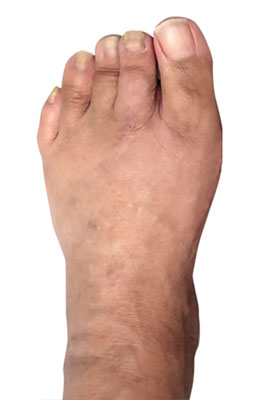

Before

Minimally Invasive Bunion Surgery before

After

Minimally Invasive Bunion Surgery after

Minimally Invasive Bunion Surgery featuring the miniBunon™ System and Tailors Bunionectomy

Melissa is a 32-year-old businesswoman who could not be off her foot post-surgery, yet she had a severely painful bunion. We performed our miniBunon™ System (our trademarked minimally invasive bunion surgery) and had a dramatic correction with no downtime. Melissa continued to work after her bunion surgery and was back in shoes and full activity at 5 weeks. Melissa could not believe the results of her Bunionectomy resulting in no bony bump, no scar and amazing motion. “After” picture taken immediately following surgery. Note the bunion and bunionette (Tailor’s bunion) in the before picture.